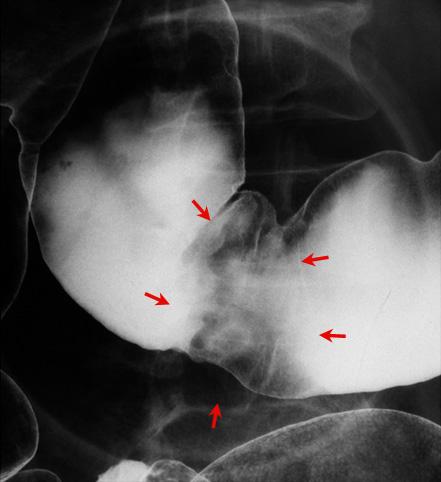

A case of varix localized at the transverse colon.

Tumor-like lesions/varices

Large intestine(Colon)/Transverse colon

X-ray

30 - 34